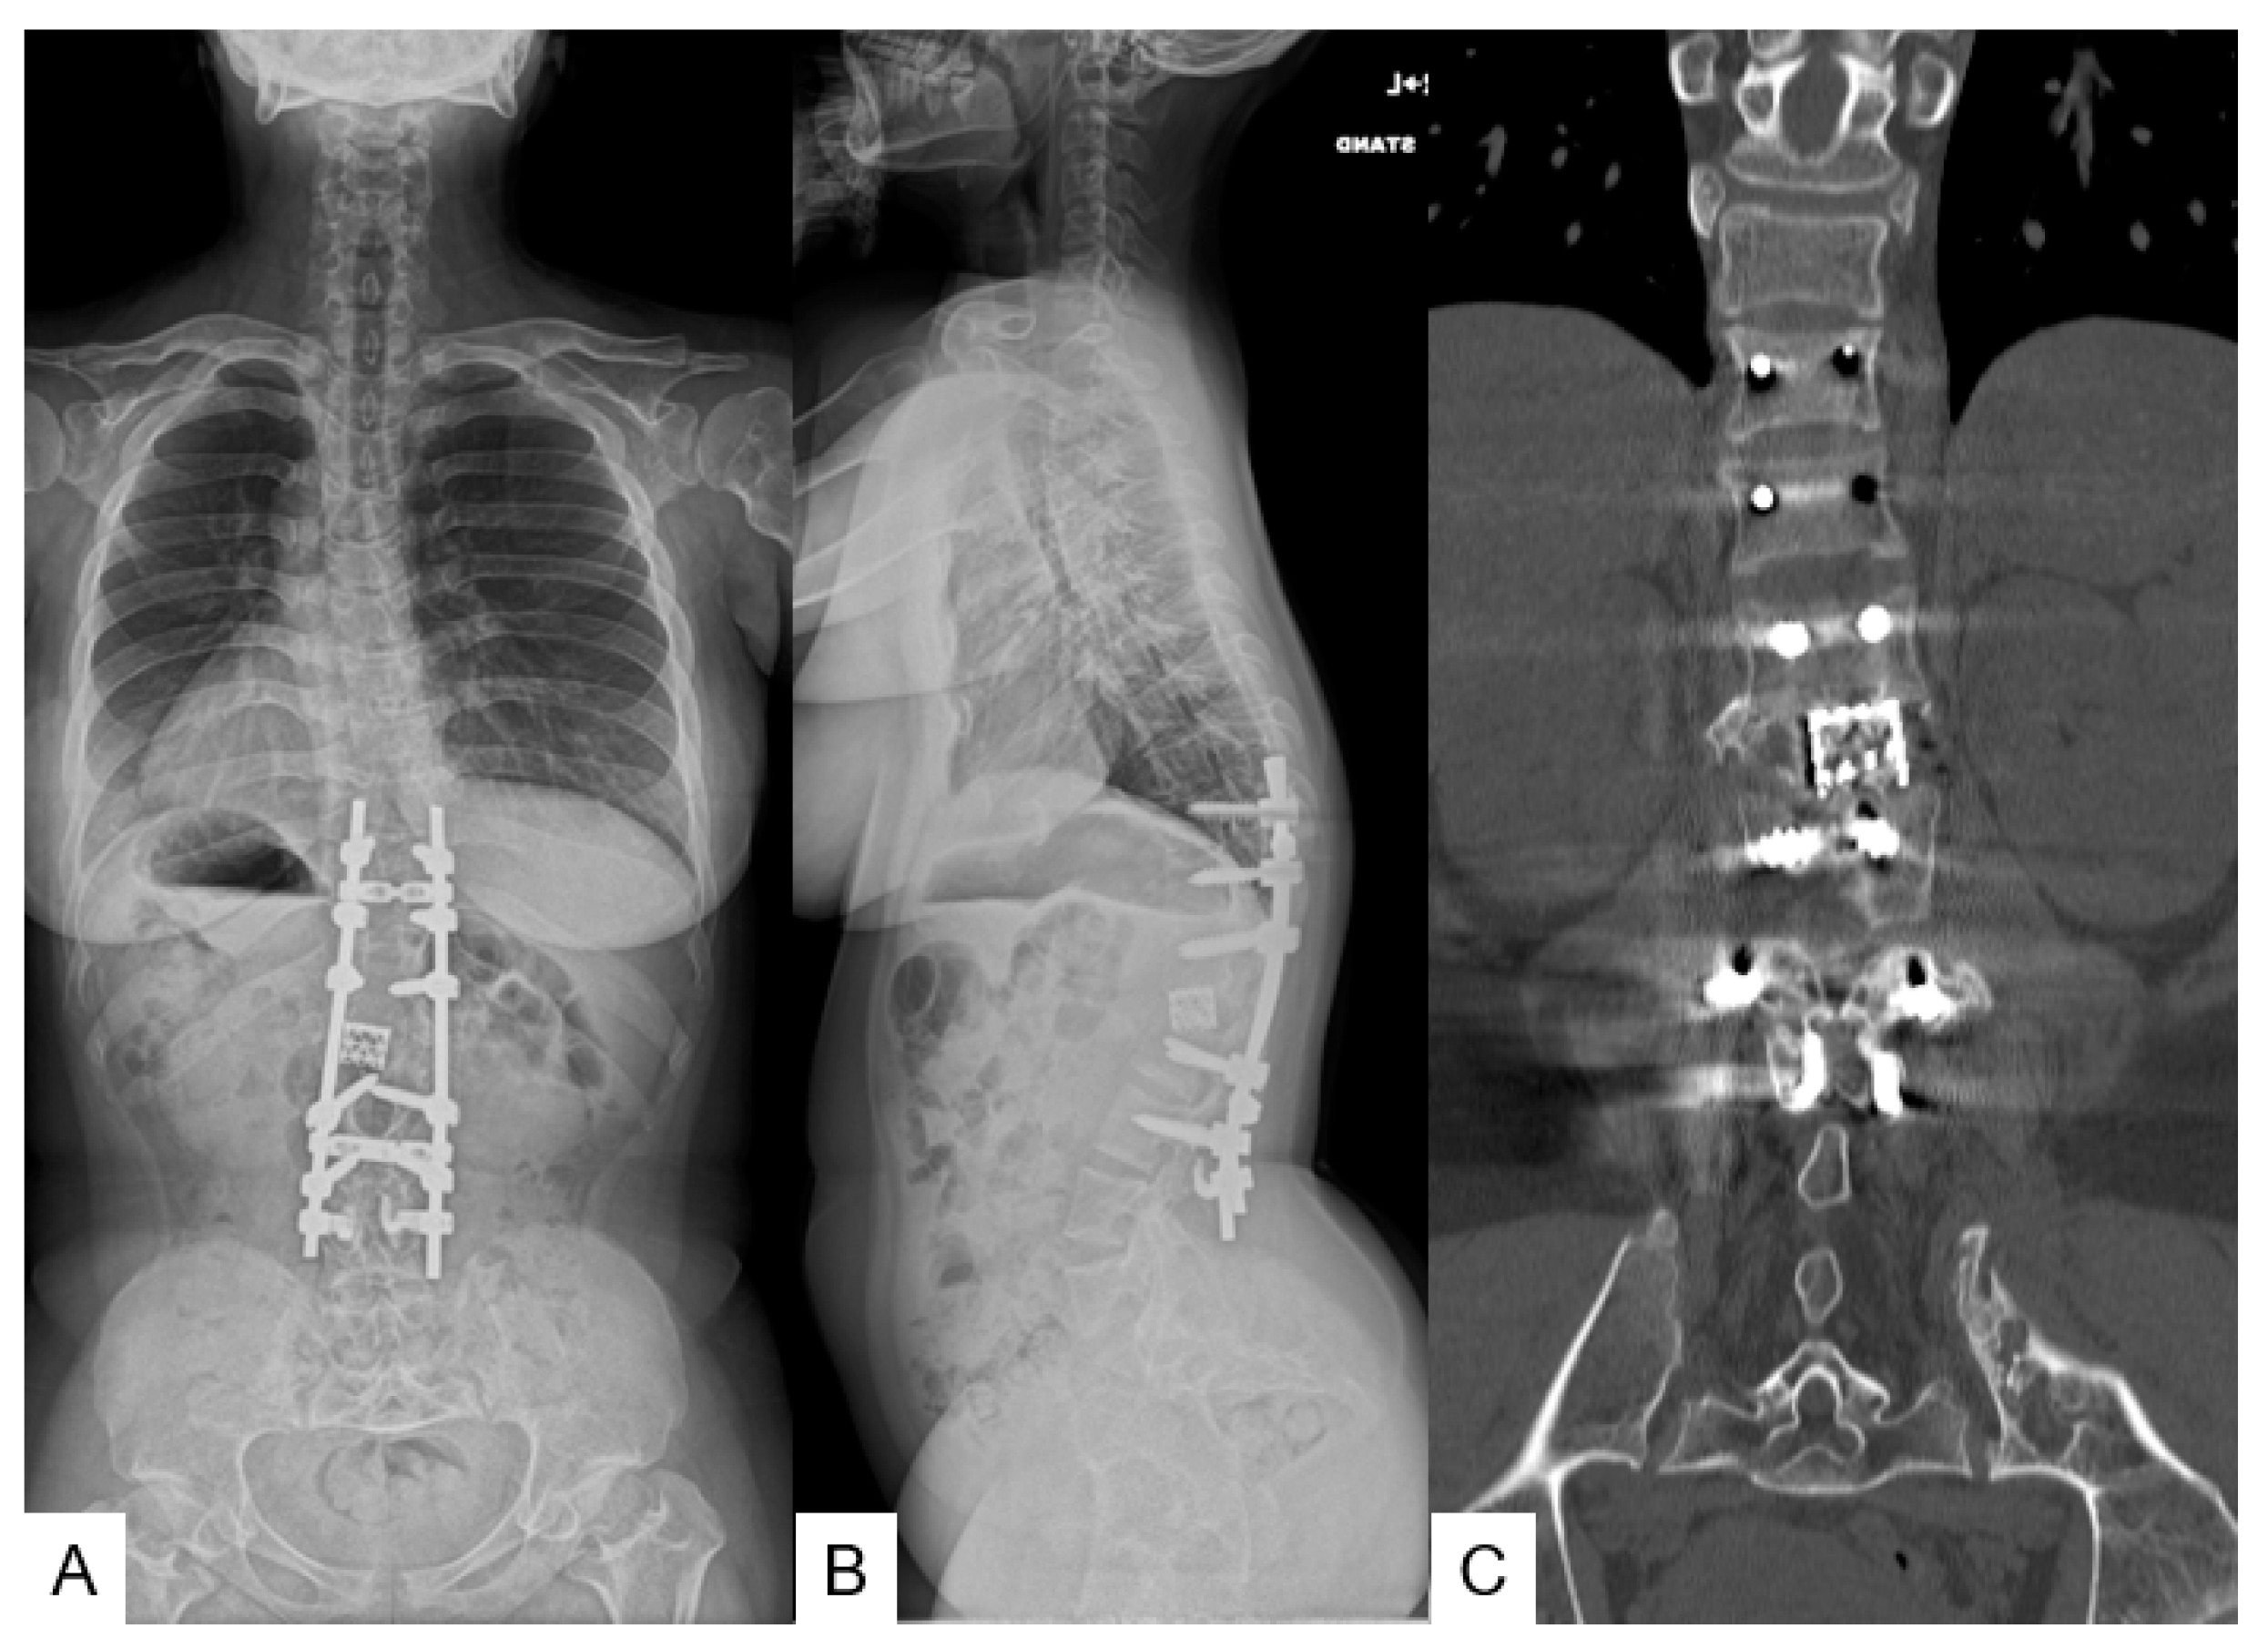

3.1.5. Postoperative Imaging

3.1.6. Follow-Up Results